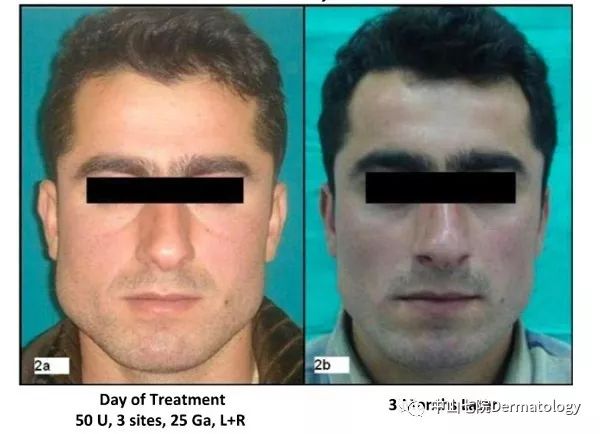

(2)轮廓塑性:以瘦脸为例,一部分人群脸大主要是因为咬肌肥大,肉毒素通过选择性萎缩部分肌肉从而让你瘦脸不是梦!!瘦腿瘦肩是一个道理,只是作用于不同的肌肉。

瘦脸